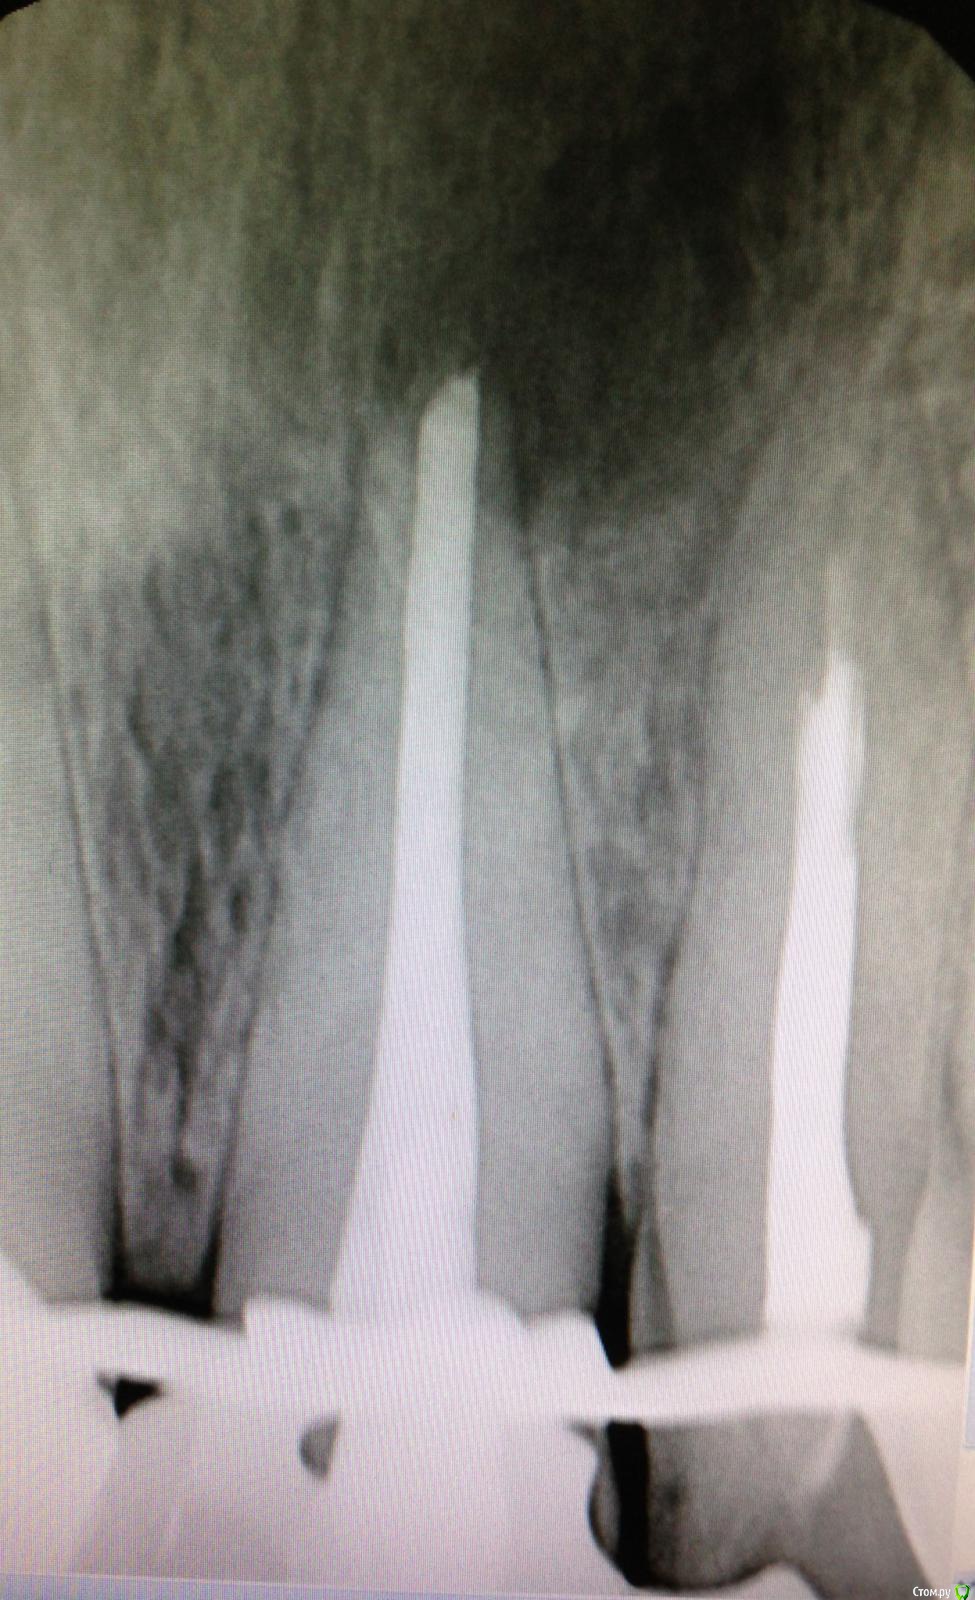

SSTi Опубликовано 4 февраля, 2015 Автор Поделиться Опубликовано 4 февраля, 2015 45. Многострадальный. 1- изоляция. Преп. Извлечения штифта. 40.04-70.02. Гх-эдта-гх уз - эдта - кальций. ЦемилайтПериостотомия2- изоляция- преп- эдта- гх уз - аспирация - перекись - хг. ОбтурацияЛатералка с модификацией) 4 1 Ссылка на комментарий